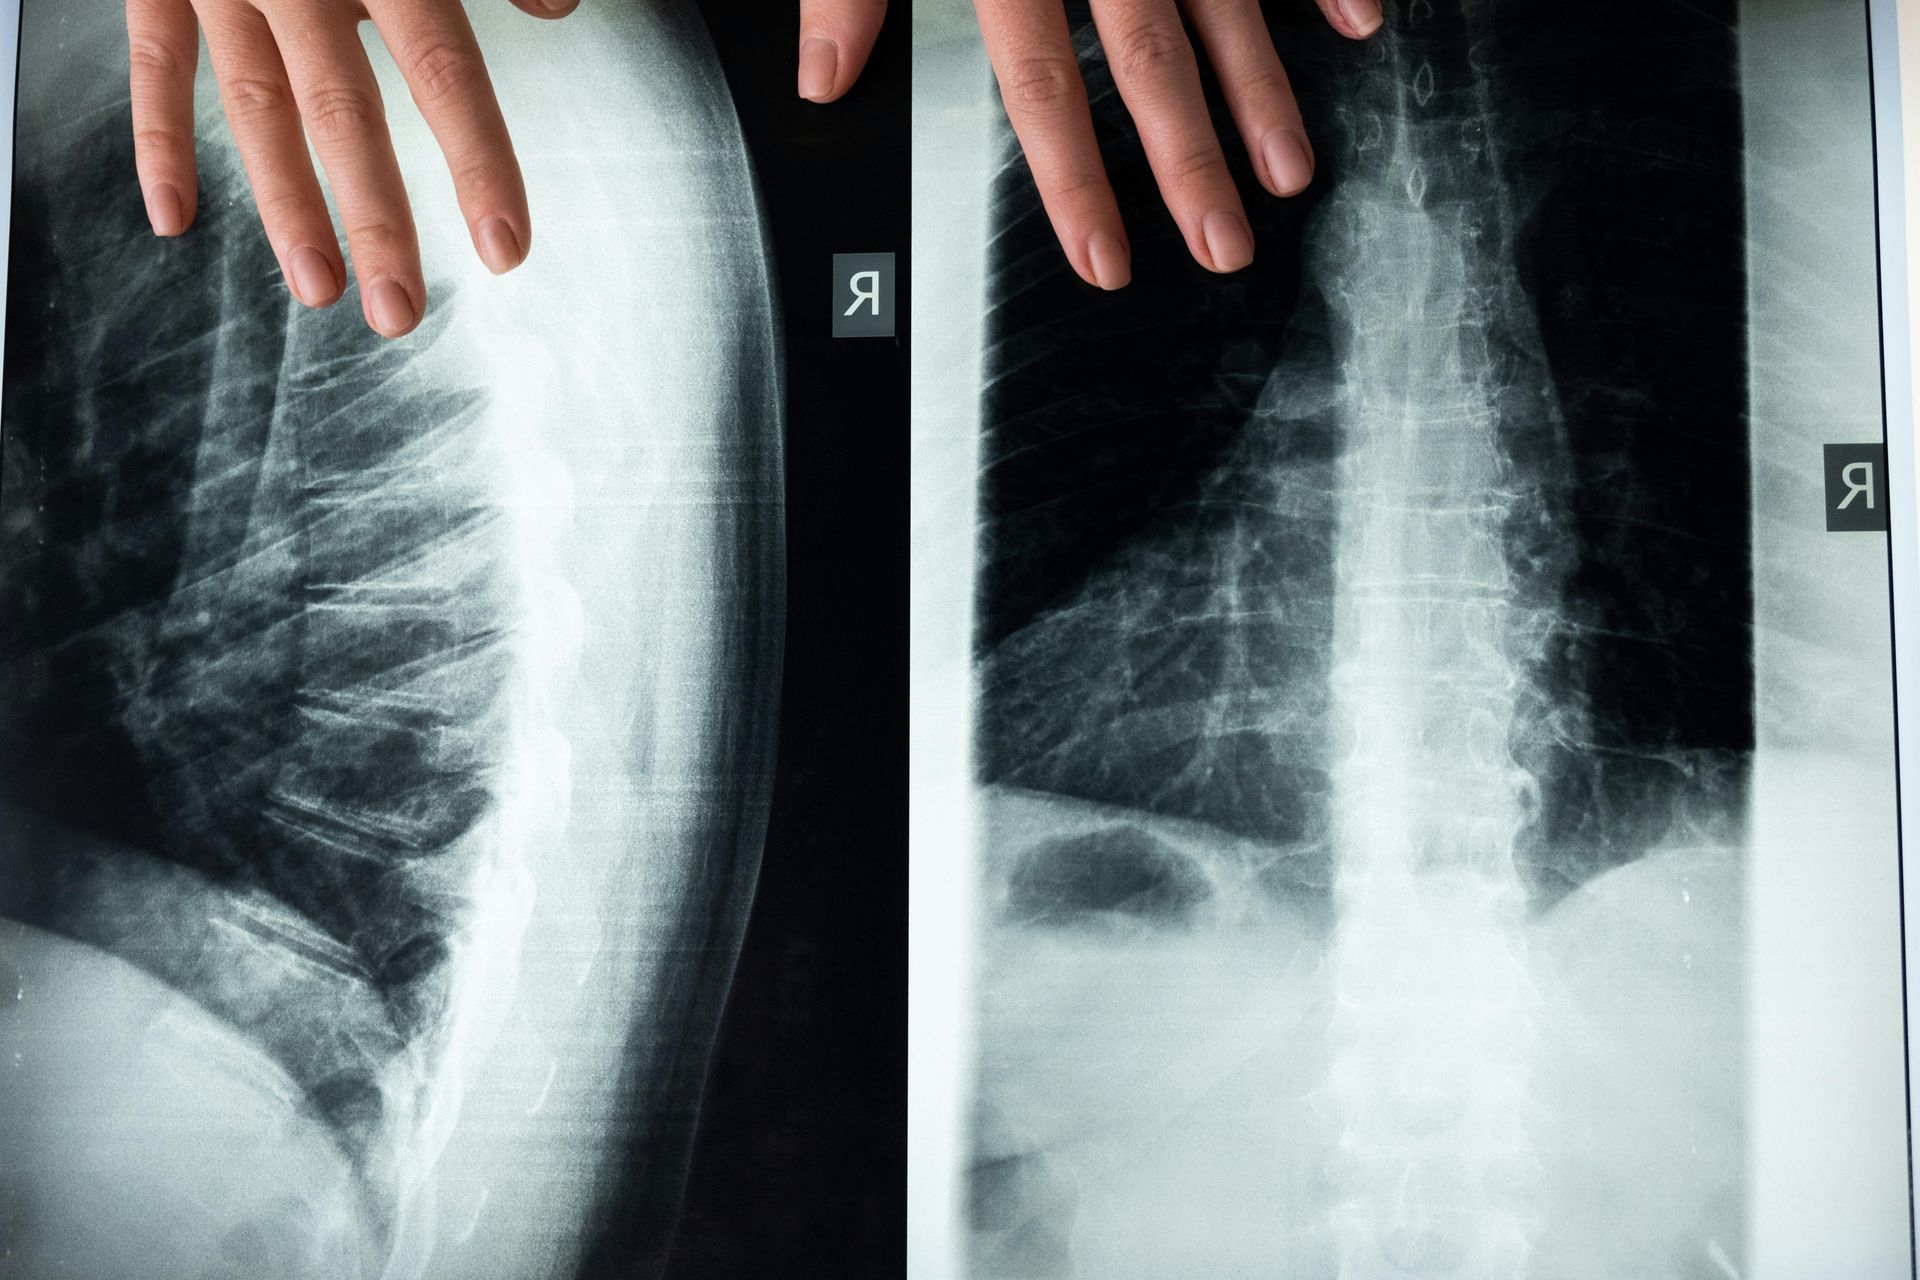

What is spinal traction therapy?

Spinal traction therapy is a treatment that gently stretches the spine to reduce pressure on discs, joints, and nerves, helping relieve pain and improve mobility.